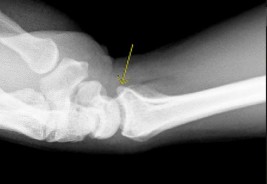

. - الأشعة المقطعية (CT Scan): توفر صوراً تفصيلية ثلاثية الأبعاد للعظام، وهي مفيدة جداً لتقييم الكسور المعقدة، مثل كسور العظم الخطافي (Hamate Hook Fracture) التي قد لا تظهر في الأشعة السينية العادية

، أو لتقييم مدى تدهور العظم في حالات مثل مرض كينبوك. - التصوير بالرنين المغناطيسي (MRI): ممتاز لتقييم الأنسجة الرخوة مثل الأربطة، الأوتار، الأعصاب، والعضلات. يكشف عن التمزقات،